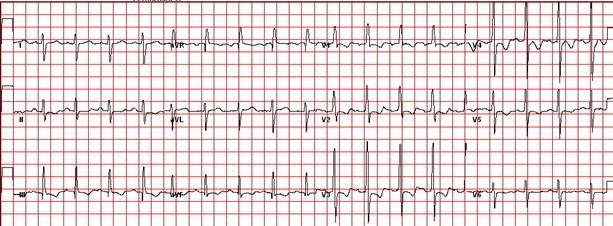

1. Який попередній діагноз? Яке ускладнення розвинулось у дитини? Опишіть патологічні зміни в аналізі крові, на ЕКГ, ЕхоКГ та на рентгенограмі.

2. Оцінити ЕхоКГ та ЕКГ.

На ЕКГ – ознаки гіпертрофії правого шлуночка із систолічним перевантаженням. Рентгенографія ОГК – заокруглення контурів серця, вип’ячення другої дуги по лівому контуру серця, збільшення правого передсердя та шлуночку, збіднення легеневого малюнку.

ЕКГ: синусова тахікардія, перевантаження правого передсердя, помірна гіпертрофія обох шлуночків.